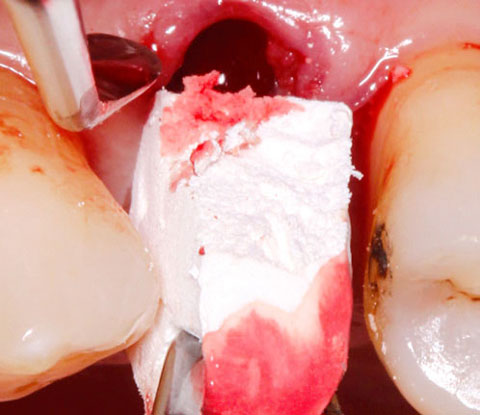

Applikation von OSSIX™ Bone in eine Extraktionsalveole ohne Lappenpräparation: Nach der Zahnextraktion (li) wird OB mit Defektblut getränkt (Mi) und vorsichtig bis zum krestalen Level in die Alveole eingebracht (re). Mit freundlicher Genehmigung von Dr. Fred Silva, USA.